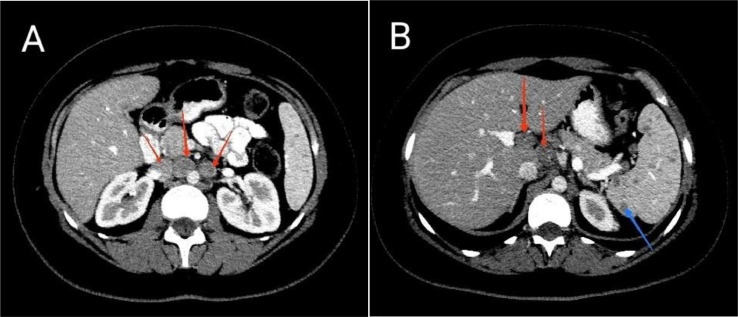

A 27-year-old woman was referred to our center complaining of jaundice and itching a month ago, along with generalized abdominal pain, nausea “non-bloody vomiting,” weakness, and weight loss of 5 kg. She was infected with COVID-19 about 6 months ago and was also treated with prednisolone 5 mg daily since 5 months ago due to subacute thyroiditis. The patient had been using ursodeoxycholic acid “famotidine montelukast hydroxyzine‚” and doxepin prescribed by a general practitioner for itching. She does not drink alcohol and does not smoke, and had no recent trips or family history of liver diseases. Laboratory tests showed an increase in liver enzymes, such as AST 96 U/L (NV < 35)‚ ALT 116 U/L (NV < 35)‚ ALP 1244 U/L (NV < 150)‚GGT 162 U/L (NV < 30)‚ total bilirubin 17.6 mg/dL (NV < 1.2)‚ direct bilirubin 10.6 (NV < 0.2). PT, PTT and INR were normal. The hemogram showed microcytic anemia with increased Ferritin and decreased TIBC (WBC = 4400 Hb = 7.9, MCV = 69.5, Plt = 371,000, Ferritin = 417 [NV = 10-124]‚ TIBC = 197 [250-450]). Thyroid function tests‚ viral hepatitis serologies‚ and other infectious disease panels‚ including HIV‚ CMV‚ and mononucleosis‚ were negative. Serum Ceruloplasmin‚ urine copper level‚ and serum protein electrophoresis were normal. ANA‚ Anti-dsDNA‚ ASMA‚ AMA‚ P-ANCA‚ C-ANCA and anti-LKM-1 were normal. An abdominal ultrasound and spiral CT scan showed multiple small lesions in the spleen and some porta hepatis‚ portocaval ‚and paraaortic lymphadenopathies with maximum SAD = 15 mm (Fig. 1). Due to the lesions seen in spleen and abdominal lymphadenopathies‚ which were suspicious for lymphomatous involvement‚ spiral neck and chest CT scans were performed and showed multiple cervical‚ mediastinal and right paratracheal lymphadenopathies (Fig. 2). The liver and biliary ducts were normal in ultrasound and MRCP.

Fig. 1.

Axial section Abdominal CT scan with IV contrast. (A) Paraaortic and aortocaval lymphadenopathy (red arrows). (B) Porta hepatis lymphadenopathy (red arrows) and multiple hypodense splenic lesions (blue arrow).